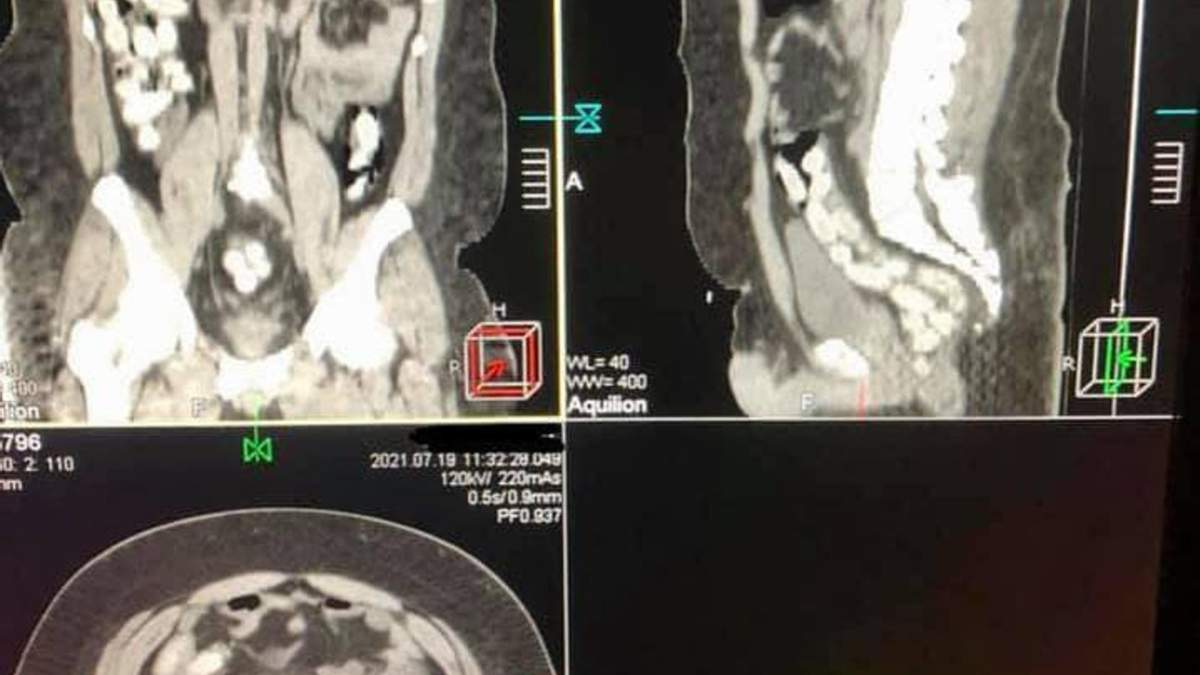

В желудке мужчина пытался перевезти 90 капсул с кокаином. После компьютерной томографии их изъяли из кишечника медикаментозным путем.

Обвинения в отношении перевозчика кокаина в желудке направлены в суд. В июле 2021 года в Борисполе задержали бразильца, который в желудке ввез в Украину почти 1 килограмм кокаина, – говорится в сообщении.